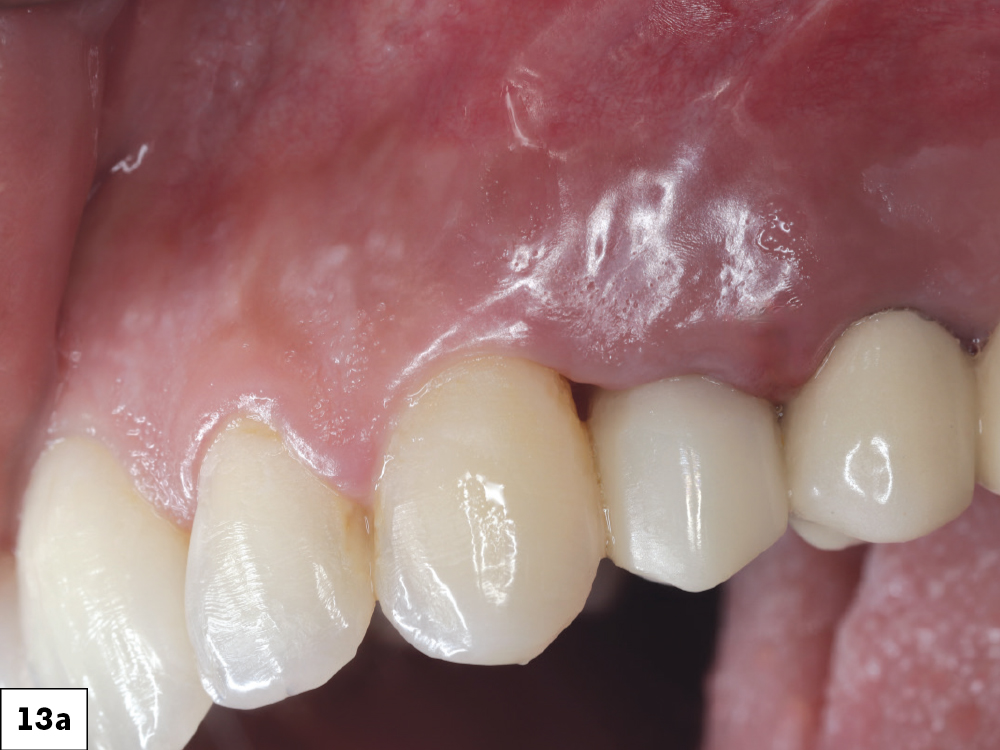

At the one-week follow up, both implants demonstrated excellent integration with healthy peri-implant tissues and no inflammation-a

At the one-week follow up, both implants demonstrated excellent integration with healthy peri-implant tissues and no inflammation-b

At eight weeks, mature keratinized mucosa framed the zirconia crowns with stable crestal bone levels and ideal emergence profiles were confirmed radiographically-c

At eight weeks, mature keratinized mucosa framed the zirconia crowns with stable crestal bone levels and ideal emergence profiles were confirmed radiographically-d

Figures 13a–13d: At the one-week follow up, both implants demonstrated excellent integration with healthy peri-implant tissues and no inflammation. At eight weeks, mature keratinized mucosa framed the zirconia crowns with stable crestal bone levels and ideal emergence profiles were confirmed radiographically.